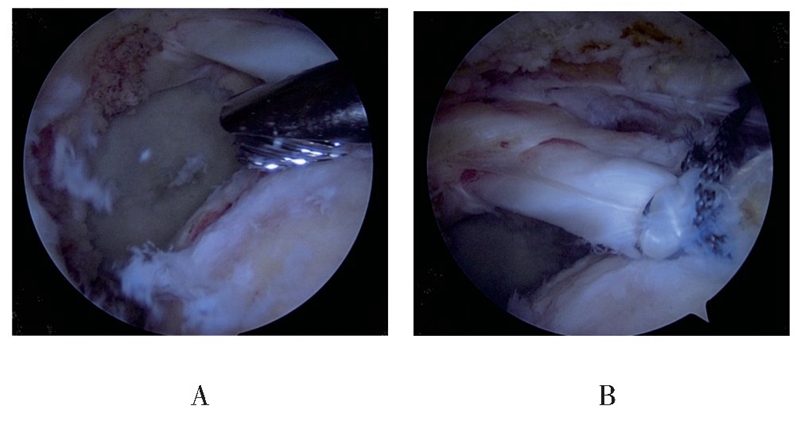

(1)首先外侧入路关节镜下观察评估肩袖撕裂及回缩情况,探查LHBT连续性及肌腱质量,术中确定肩袖为巨大撕裂,累及2根肌腱以上且冈上肌腱回缩明显,松解后仍难以拉回足印区或虽可拉回足印区,但张力较大,同时LHBT无明显撕裂或退变时,开始进行“Chinese Way”肩袖修补程序(见图1)。

图1 关节腔探查见LHBT连续性良好,无明显撕裂及严重退变(A);肩峰下间隙探查见后上方巨大肩袖撕裂,其中冈上肌腱回缩严重(B)

图2 骨性刨削清理冈上肌腱足印区(A),移位固定LHBT至冈上肌腱足印区(B)

图3 组织抓钳牵拉后方撕裂肩袖,判断肌腱张力及撕裂形态(A),在移位固定的LHBT后方植入2枚带线锚钉,连同缝合固定LHBT的缝线一起缝合冈下及部分冈上肌腱(B)